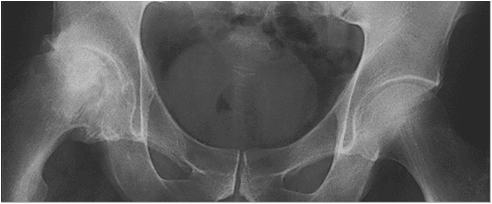

Arthritic Hip (left) Healthy Hip (right)

All joints have a smooth white slippery covering called cartilage which acts as the bearing surface for movement. It is where the “rubber hits the road” for the movement of joints. There are over 100 various disorders which cause damage to the cartilage. The most common arthritis, osteoarthritis, results from stresses on cartilage that are greater than the tissue can withstand. This can be routine forces on weakened cartilage or from excess forces on normal cartilage. Researchers have found that an inherited weakness of the main protein in cartilage (collagen) frequently leads to early osteoarthritis. Hormones that help make women’s tissues soft, supple and more flexible for pregnancy may be a reason women have twice the osteoarthritis of men. It is easy to understand how the forces of direct trauma can damage cartilage and its underlying bone. Motor vehicle accidents, falls or severe sports injuries, especially those that tear ligaments, are well known causes of arthritis later in life. Using a tire example, driving recklessly over potholes or across sharp metal objects will clearly tear up your tires! Excess force on the joint over the long term can also wear out healthy cartilage.

People with crooked legs from bowlegs or knock-knees or from poorly healed fractures of the leg bones, wear out their cartilage on the high stress side of their joints. People with straight legs can also overload their cartilage with continuous loads that crush their cartilage. Participation in high level sports like soccer and football has also been associated with more frequent arthritis of the hip and knee. Occupations where heavy loads are lifted repeatedly, such as farming and ranching, can also lead to arthritis. Being overweight causes heavy loads across your joints with every step. Obesity is not only a common cause of hip, knee, and ankle arthritis, but it also makes your symptoms worse.